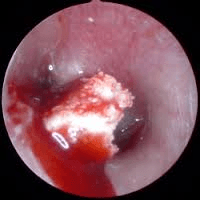

Trauminė būgnelio perforacija

Trauminė būgnelio perforacija sukeliama tiesiogiai pradūrus būgnelį, pliaukštelėjusper ausį, sprogimo metu ar dėl barotraumos. Labai dažnai trauminė būgnelio perforacija įvyksta nukritus į vandenį čiuožiant vandens slidėmis. Būdingas stiprus ir staigus ausies skausmas, susijęs su trauma, kuris vėliau sumažėja, staigus klausos pablogėjimas, ūžesys. Otoskopuojant matyti šviežio kraujo išorinėje klausomojoje landoje, matoma būgnelio perforacija nelygiais kraštais. Nedidelės perforacijos sugyja savaime, tačiau reikėtų saugoti, kad į ausį nepatektų vandens. Didesnės perforacijos, ypač kai užsilenkia kraštai, gydomos chirurgiškai, atliekant timpanoplastiką. Jei perforacija atsirado įkritus į vandenį ar pradūrus būgnelį, supūliavimo profilaktikai reikėtų apie savaitę laiko palašinti antibiotikų lašų į pažeistą ausį. Taip pat reikėtų vengti vandens patekimo į pažeistą ausį kol būgnelis sugis ar bus atlikta operacija.